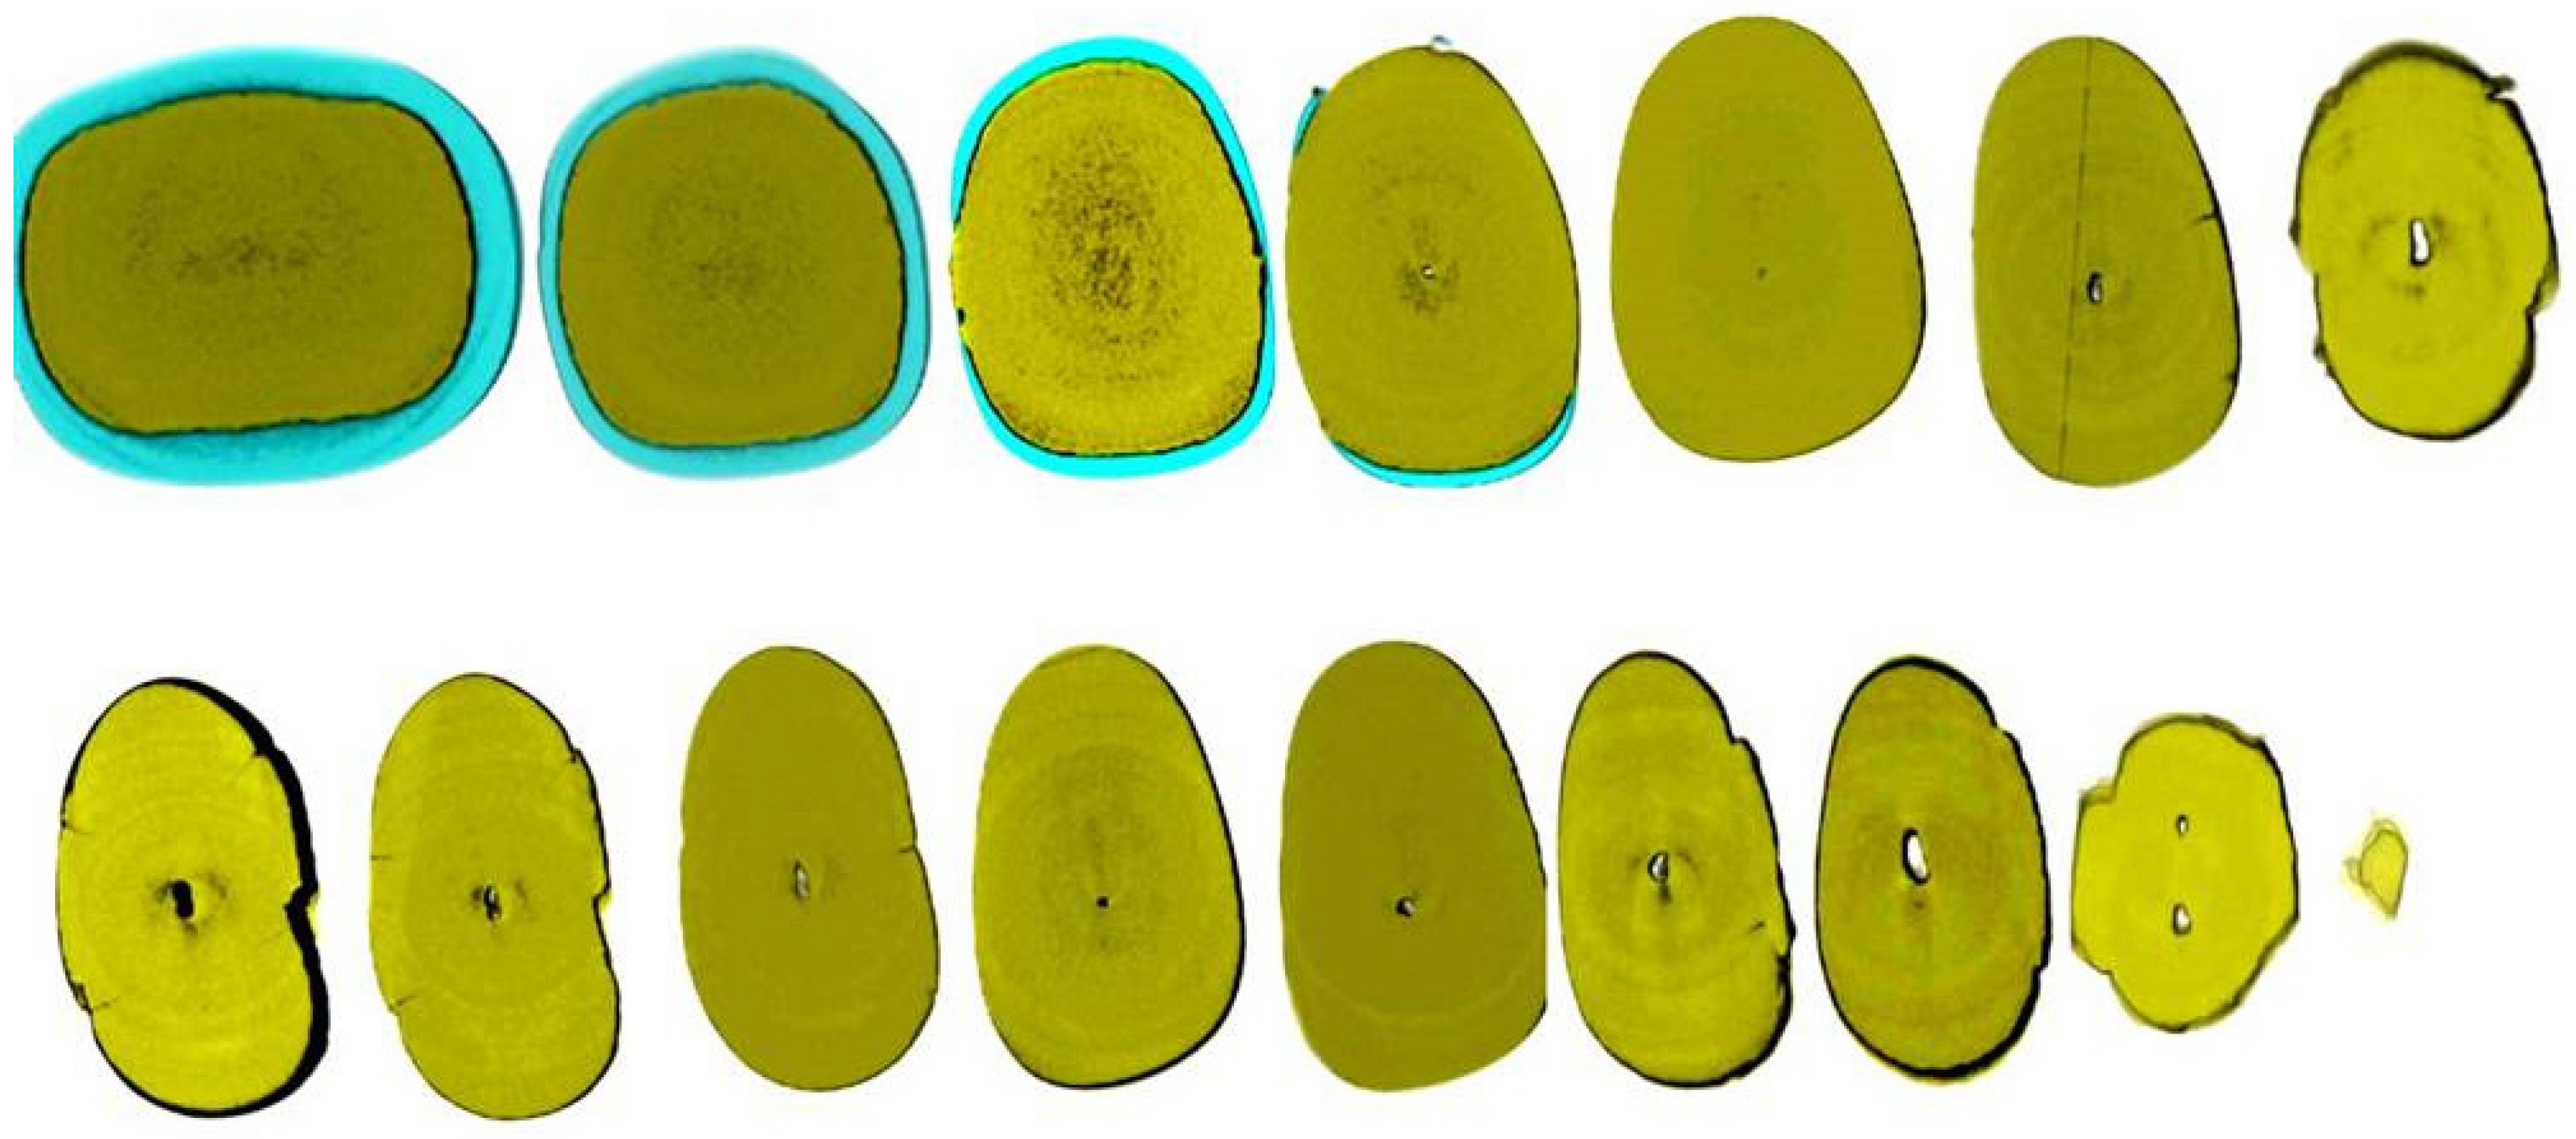

Figure 3.

Histological images of the calcified vital pulp tissue that was removed during the root canal treatment of a second mandibular molar with deep periodontal distal lesion suffering from symptomatic irreversible pulpitis. Notice the linear calcified nodules formed along the root pulp vessels (hematoxylin–eosin staining) (clinical and radiographic images are courtesy of Dr. Chaniotis Antonis, and histological images are courtesy of Prof. Domenico Ricucci).

Figure 4.

Removal of a pulp stone from a second mandibular molar suffering from irreversible pulpitis. Micro-ct evaluation of the external and internal structure of the pulp stone. Notice that the structure of the pulp stone is not solid, presenting an internal network of unmineralized tissue. The clinical significance is that the pulp stones can be dissected in smaller pieces and removed (clinical, radiographic, and micro-CT images courtesy of Dr. Chaniotis Antonis).

Figure 5.

The free pulp stone’s histology shows distinct calcified nodules growing around a network of unmineralized extracellular matrix material and capillary vessels (hematoxylin–eosin staining) (histological images courtesy of Dr. Chaniotis Antonis).